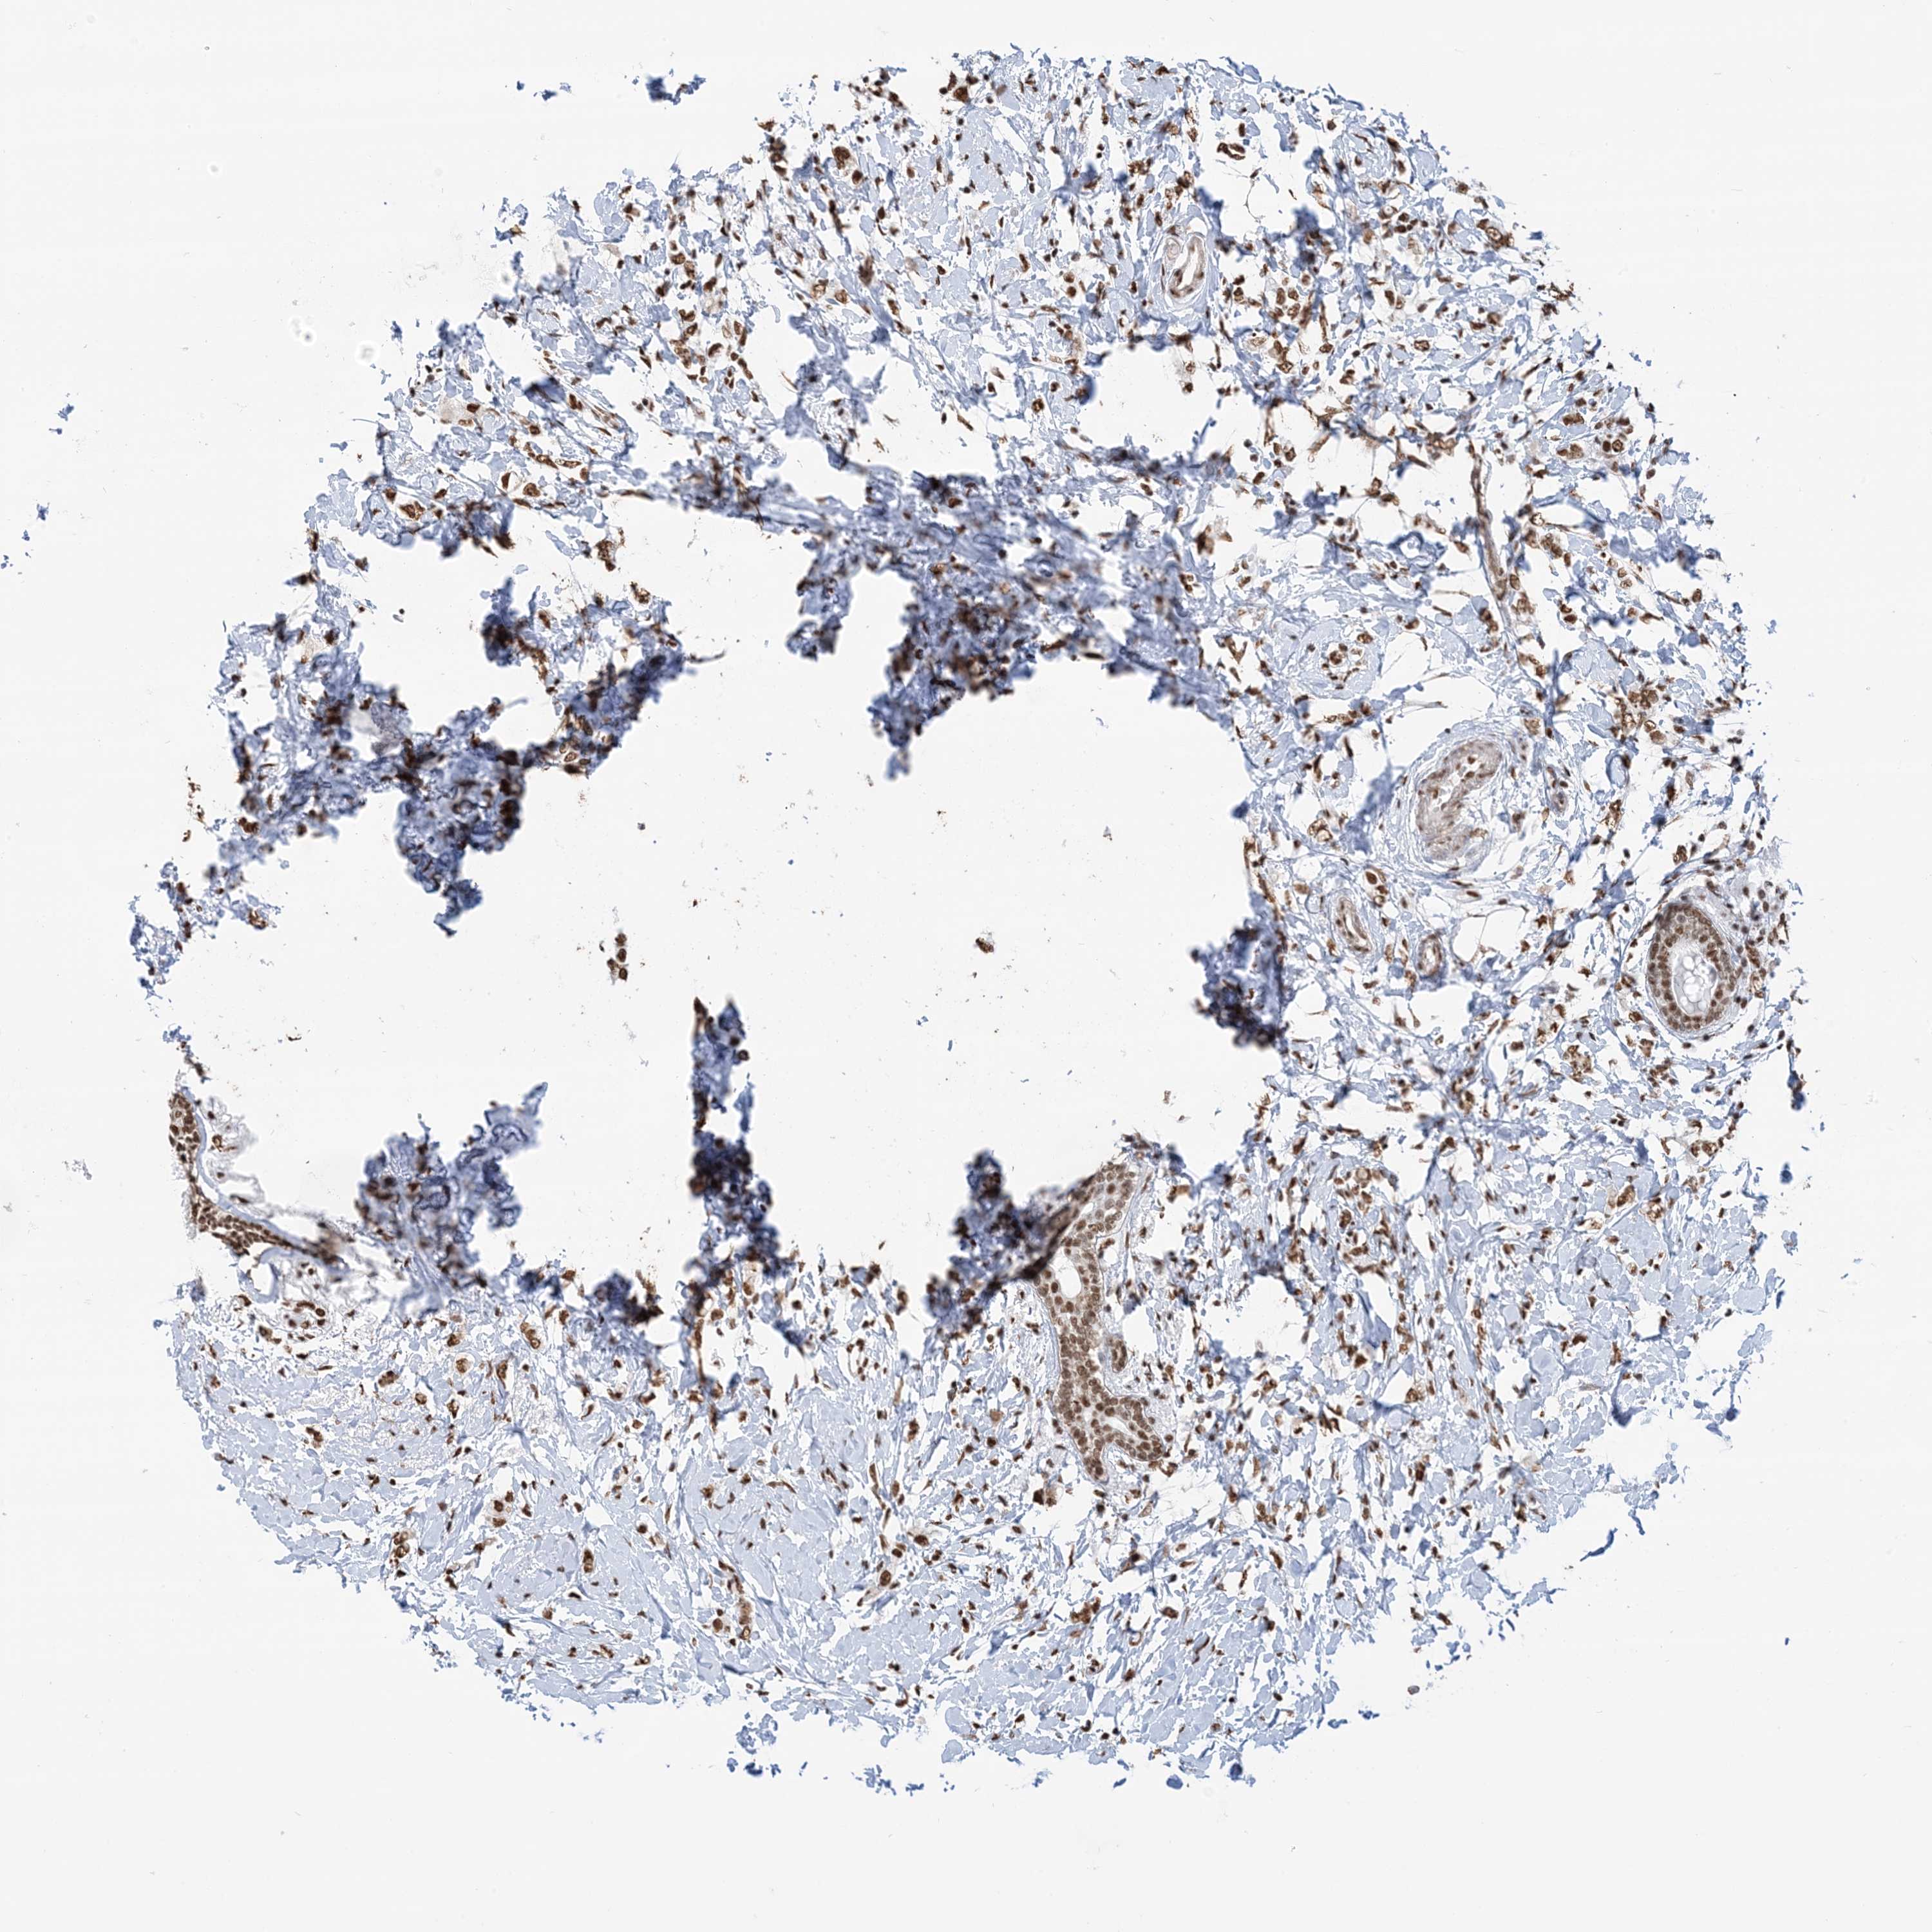

BRCA TCGA BRCA VALIDATION PROTEIN EXPRESSION